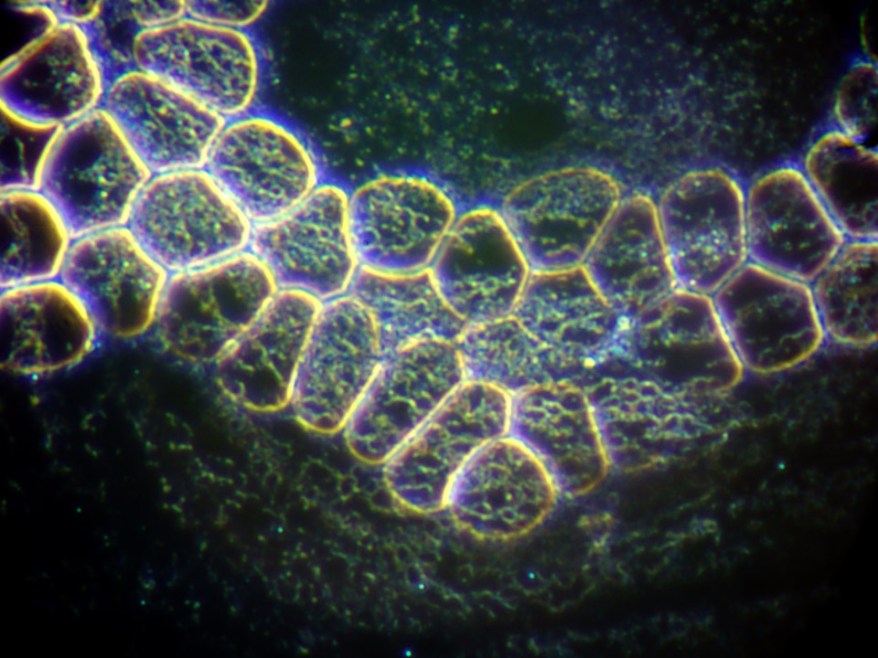

Microscopy of Spirochaete Biofilm